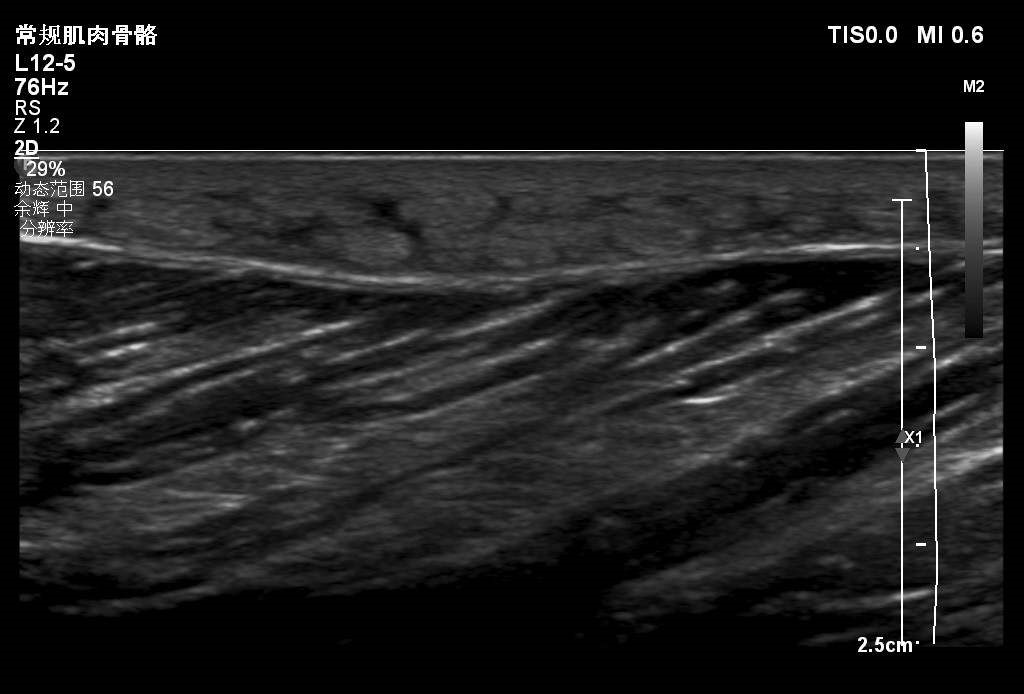

患者大腿远端浅表可见一包块隆起,自述半月前出现红肿,目前未见明显红肿,触摸感觉微痛。

根据病情考虑可能蚊虫叮咬水肿。大家考虑是什么?有没有专家给看看,是什么?谢谢。